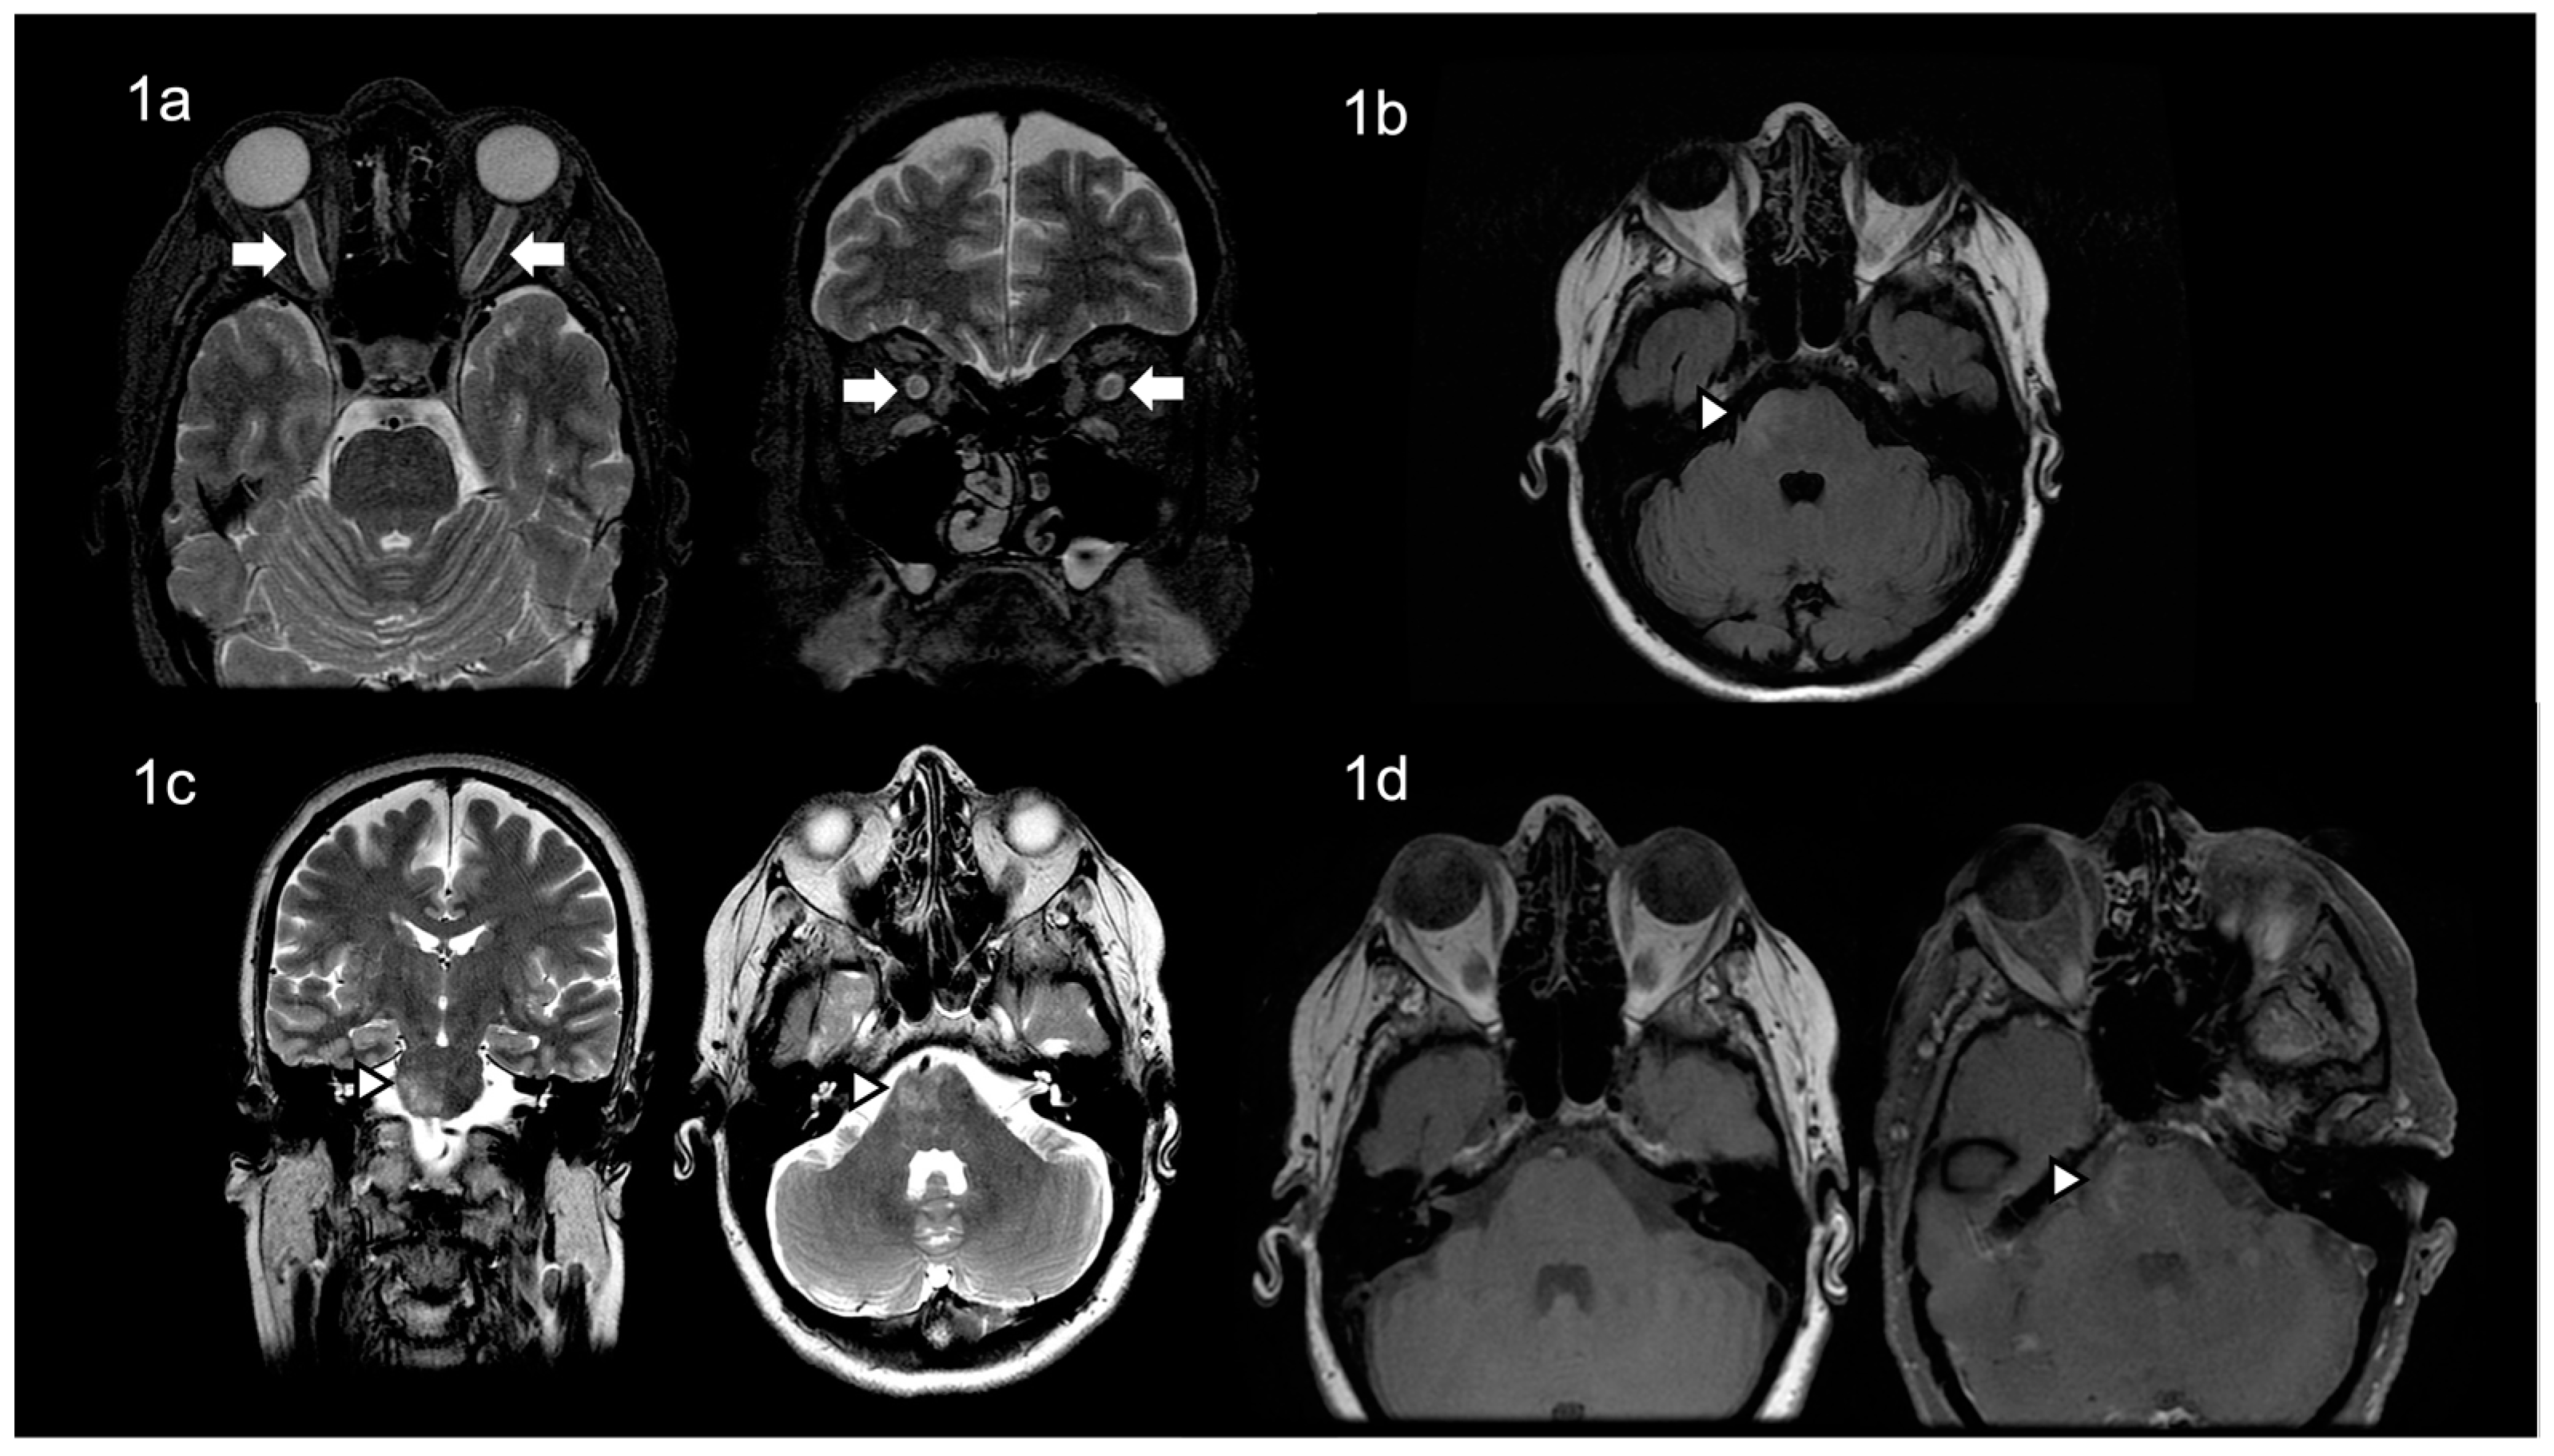

2. Case Presentation